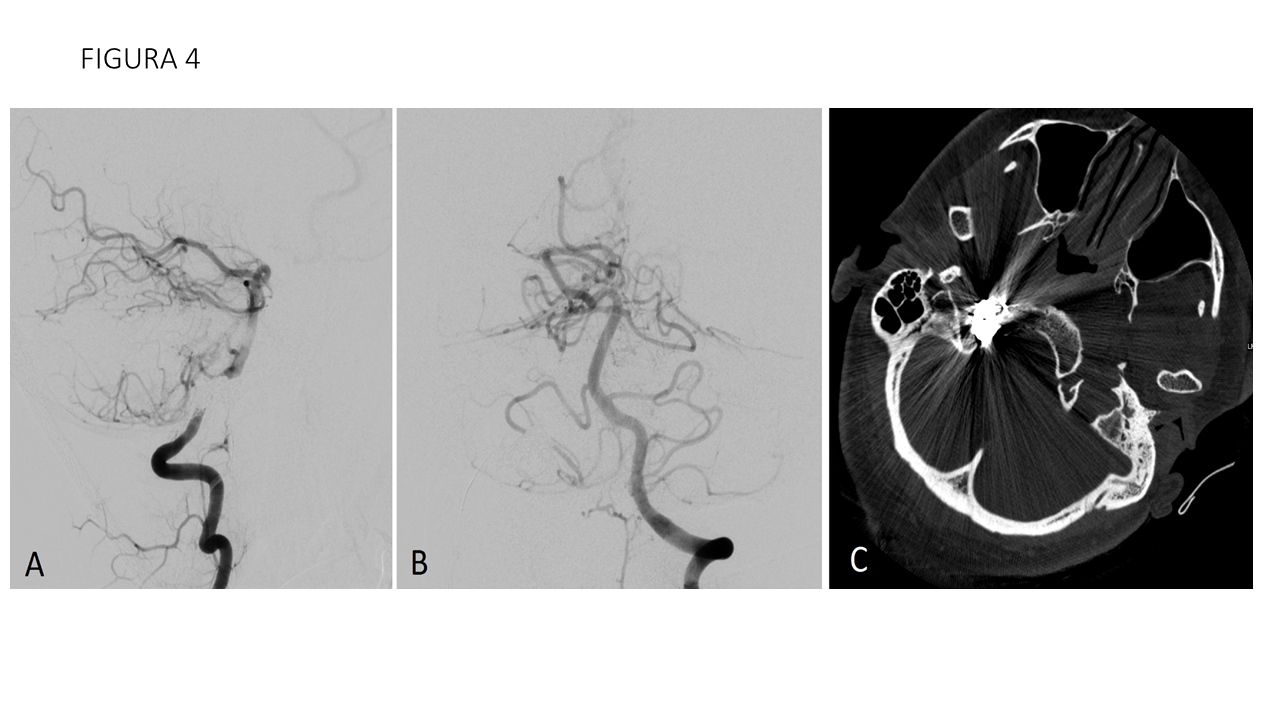

FIGURA 4 Series de control tras tratamiento desde ambas arterias vertebrales (A y B) no muestran aportes arteriales ni opacificación venosa precoz que sugiera shunt arteriovenoso (fístula arteriovenosa dural). TC de cráneo (C) muestra el nido de coils en el canal hipogloso derecho.